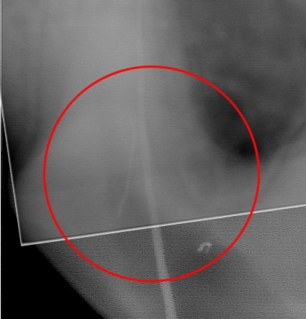

まずは残存ファイルのある根管を見ていきましょう。

画像の丸で囲ってある部分に破折したファイルが認められます。

根管の位置を実際に想像してみることが大切です。根管のアクセスした部位からはより遠位であることがわかります。デンチンの厚さを想像しながら探っていきます。またこの位置にはもう一本の根管が存在するために削っていくこと、探すことに専念しすぎるとパーフォーレーションを起こし、もう一本の根管口を見失う可能性があります。ですから、折れたファイルを探すことへの焦りを捨て、まずはもう一本の根管拡大を終了させ、確実にその根管をとらえられるようにすることが大切です。

かなり削りましたが、この状態で初めて破折ファイルを目視することが可能となります。レントゲンではわかりやすいのですが、およそ0.5~0.8mmを見ることが可能です。